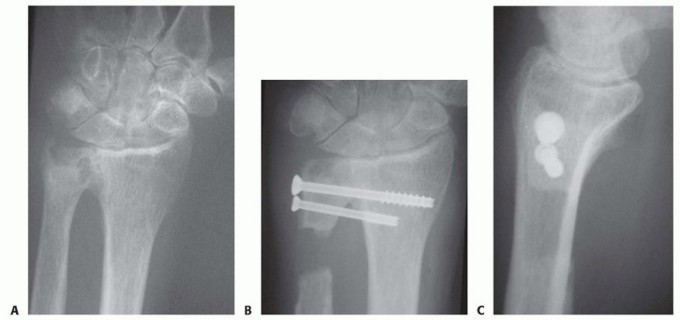

Surgical Management of Traumatic Conditions of the Elbow: Interposition Arthroplasty